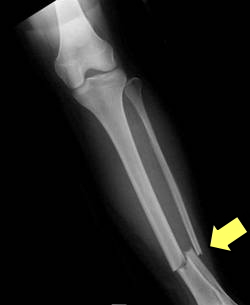

| 胸部正面像(正常) | 下腿正面像(骨折) |